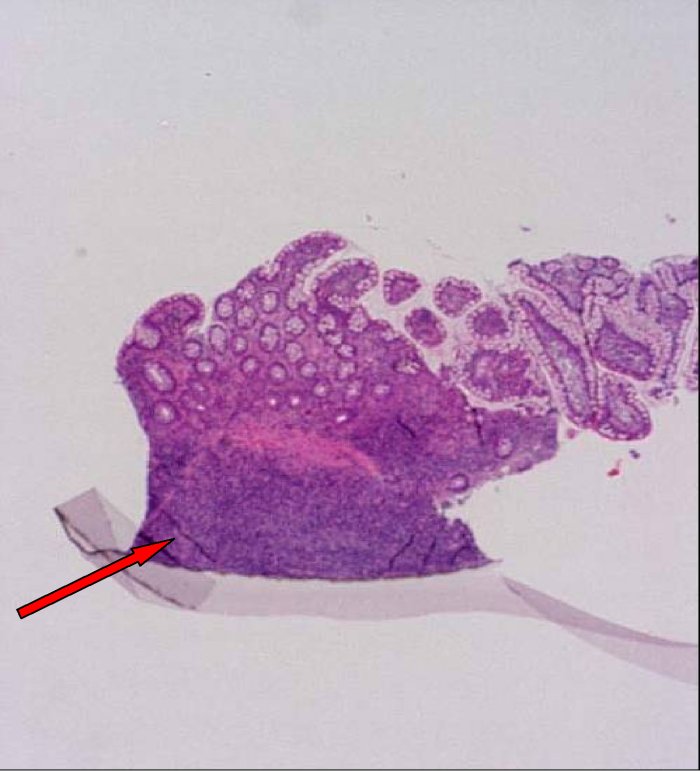

assenza di lesioni ulcero-erosive. L'esame istologico ha confermato

la presenza di noduli da infiltrato linfoide, confinato alla lamina

propria e alla superficie sottomucosa (Figura

2 a,b,c).

Figura 2 (a,b,c). Sezioni a diverso ingrandimento di mucosa di intestino con colorazione in ematossilina eosina che mostrano la presenza di aggregati linfoidi iperplastici.